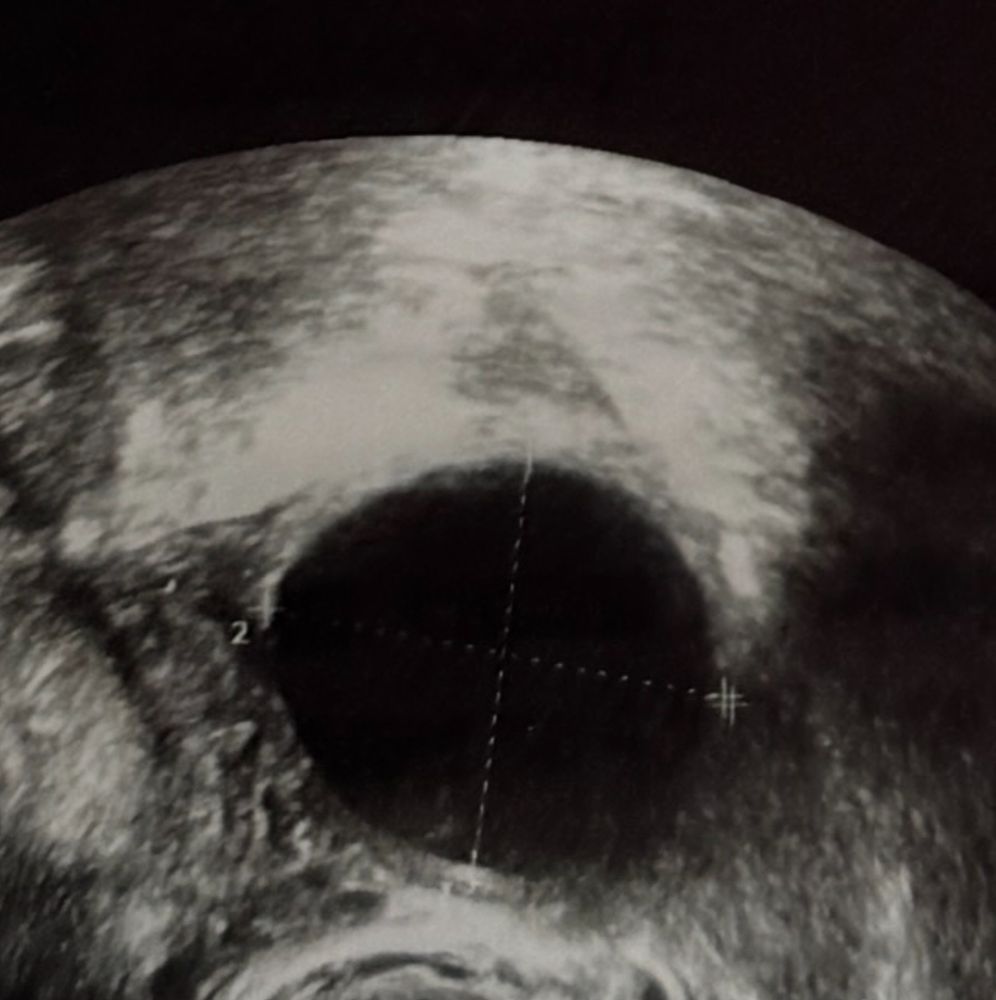

Woka woka, они знаете как пишут: на фоне жидкости в полости малого таза лоцируется округлое анэхогенное образование до 4.9мм в диаметре ( плодное яйцо?). что это значит?

Уже должно быть видно. Срок 5 недель. Есть риск внематочной, либо древний аппарат. Есть заключение? Можете прикрепить?

Алина А, узист сказала, 2-3 недели Написала так: на фоне жидкости в полости малого таза лоцируется округлое анэхогенное образование до 4.9мм в диаметре ( плодное яйцо?). что это значит?😭🙏🏻

Алина, судя по размерам это и есть ПЯ. В матке или в полости малого таза???? Это важно

Алина А, в полости малого таза…

Алина, так себе история(( судя по узи, ПЯ приквепилось вне матки и труб(((

Алина, да, либо там, либо на яичник, либо в трубе, но врач не увидела. Параовариально- значит рядом с яичником или маткой (наколько я могу судить как не врач). Размер образования соответствует сроку вашей Б.

По картине очень похоже на внематочную. Желтое тело есть. Где-то в области таза что-то похожее на плодное яйцо увидели, это может быть и в трубе… жидкость тоже один из признаков ВБ. Страшная штука у меня трубу так удалили. На ваш вопрос можно ли забеременеть, да с одной трубой можно если она проходима. Я бы сейчас сдала хгч от 1000 видно ПЯ в матке, возможно у вас поздняя овуляция и просто не видно на узи еще ничего. Так что пока отставить панику, верим в лучшее 🤗🙏😇

Алина, в правом яичнике почитайте это желтое тело так описано